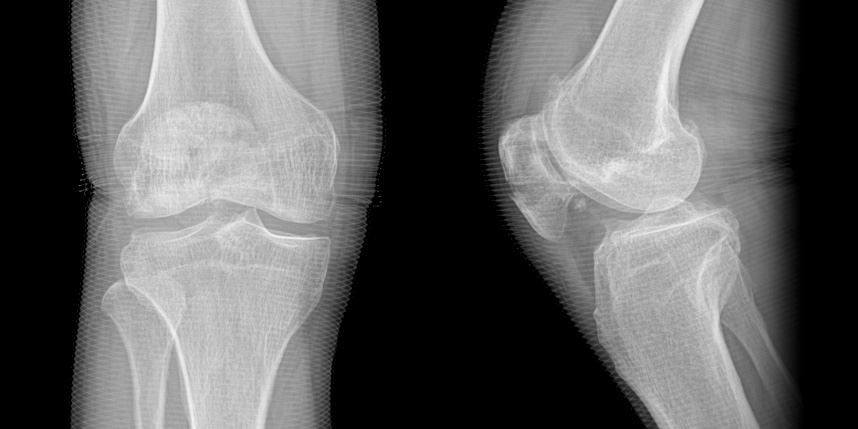

무릎 골절

* 환자에게 받은 소중한 자료입니다.